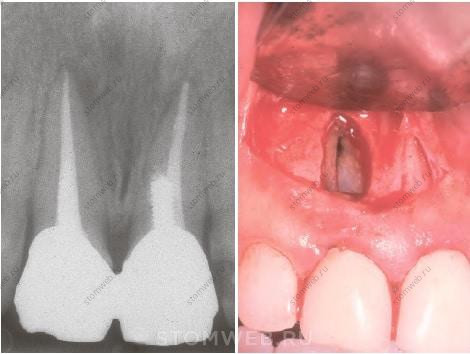

Изменения в пульпе чаще возникают в случаях центрально расположенной трещины (от одного маргинального гребня до другого через центральную ямку), чем когда трещина проходит более щечно или язычно. Такие центрально проходящие трещины обычно достигают пульпарной камеры на поздней стадии. В результате, пульпа воспаляется, а после некротизируется вследствие проникновения инфекции через трещину. Острая боль при жевании, типичная для ранней стадии, пропадает при потере жизнеспособности пульпы. Последним проявлением нелеченой продольной трещины на первый взгляд интактного моляра становится апикальный периодонтит. При некрозе пульпы на рентгенограмме появляются признаки апикальной рентгенпрозрачности, неотличимой от таковой при апикальном периодонтите (Рис. 21-6)

РИС, 21-6 Случай некроза пульпы вследствие трещины. Интактный зуб или зуб с минимальными реставрациями не должен быть девитальным. А) Данная рентгенограмма нижнего седьмого зуба с реставрацией на значительном расстоянии от пульпарной камеры; тем не менее, зуб не витален и симптоматичен. В) При исследовании жевательной поверхности обнаружена небольшая трещина на дистальном маргинальном гребне. С) После удаления зуба на мезиальной поверхности коронки и корня нет признаков трещины. D) На дистальной поверхности трещина распространяется на коронку и верхнюю часть корня. E,F) На разрезе хорошо видно, что трещина достигает пульпарной камеры.